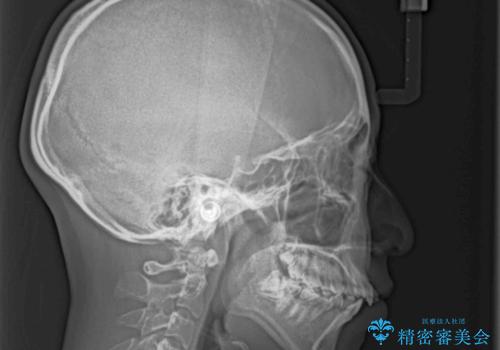

- 前歯がくちばしのように飛び出していることを気にして来院された患者様です。

唇が前方に突出している横顔が気になっているため、上下左右の第一小臼歯4本を抜歯し、ワイヤー装置にて矯正治療を行うこととしました。